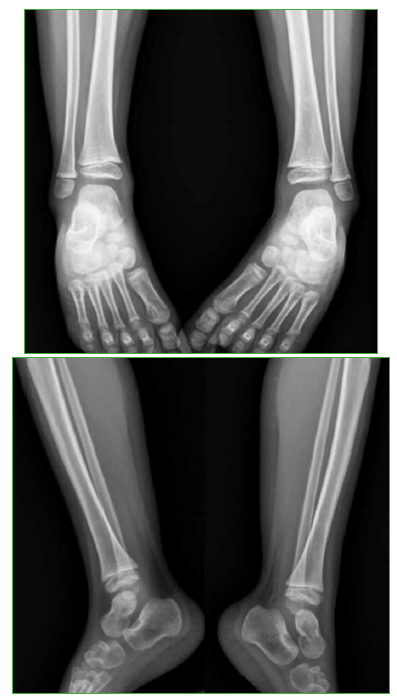

Lipoblastoma: una causa inusual de tumoración del pie en niños

65-73

Acceso mediante suscripción PDF Acceso mediante suscripción PDF_EN (English) Acceso mediante suscripción Figura 1 Acceso mediante suscripción Figura 2 Acceso mediante suscripción Figura 3 Acceso mediante suscripción Figura 4 Acceso mediante suscripción Figura 5 Acceso mediante suscripción Tabla 1 Acceso mediante suscripción HTML